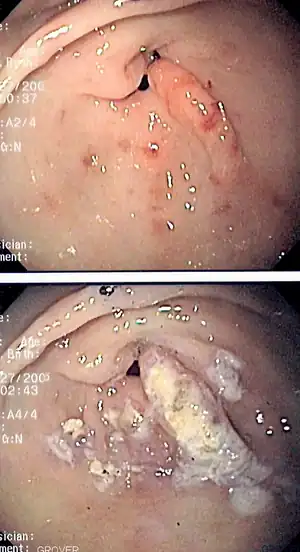

Portal hypertensive gastropathy refers to changes in the mucosa of the stomach in patients with portal hypertension; by far the most common cause of this is cirrhosis of the liver. These changes in the mucosa include friability of the mucosa and the presence of ectatic blood vessels at the surface. Patients with portal hypertensive gastropathy may experience bleeding from the stomach, which may uncommonly manifest itself in vomiting blood or melena; however, portal hypertension may cause several other more common sources of upper gastrointestinal bleeding, such as esophageal varices and gastric varices. On endoscopic evaluation of the stomach, this condition shows a characteristic mosaic or "snake-skin" appearance to the mucosa of the stomach.

The diagnosis of portal hypertensive gastropathy is usually made on endoscopy. The usual appearance of portal hypertensive gastropathy on endoscopy is a mosaic-like or reticular pattern in the mucosa. Red spots may or may not be present. The pattern is usually seen throughout the stomach.[2] A similar pattern can be seen with a related condition called gastric antral vascular ectasia (GAVE), or watermelon stomach. However, in GAVE, the ectatic blood vessels are more commonly found in the antrum or lower part of the stomach.[2]